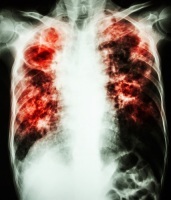

Туберкулез — инфекционное заболевание, передающееся воздушно-капельным путем. И без соответствующего лечения человек, больной активной формой туберкулеза, ежегодно может заразить в среднем 10-15 человек. По данным ВОЗ, каждый день от этой предотвратимой и излечимой болезни умирает почти 4 500 человек, а почти 30 000 человек заболевают ею (большинство из которых — жители развивающихся стран).

Туберкулез по-прежнему является ведущей причиной смертности от инфекционных болезней в мире.

Развитию туберкулеза способствует неполноценное питание, потребление токсических продуктов (табак, алкоголь, наркотики), неудовлетворительные условия труда и быта, некоторые хронические заболевания (сахарный диабет, заболевания крови, ВИЧ).